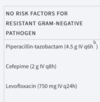

Differentiate between community-acquired and hospital-acquired bacterial pneumonias.

- HAP Tx

- If a patent has risk factors for MRSA, what do you do?

Differentiate between community-acquired and hospital-acquired bacterial pneumonias.

- Outpatient CAP Tx

- What can you give to a previously healthy patient who has not been on any antibiotics for the last 3 months?

3 options

- A macrolide

- Usually clarithromycin

- Azithromycin

- Doxycycline